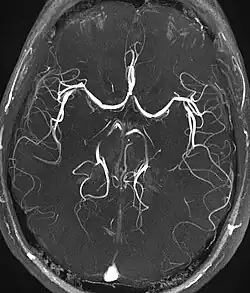

| Magnetic resonance angiography (MRA) and venography | Time-of-flight | TOF | Blood entering the imaged area is not yet magnetically saturated, giving it a much higher signal when using short echo time and flow compensation. | Detection of aneurysm, stenosis, or dissection[31] |

Magnetic resonance angiography

Magnetic resonance angiography (MRA) is a group of techniques based to image blood vessels. Magnetic resonance angiography is used to generate images of arteries (and less commonly veins) in order to evaluate them for stenosis (abnormal narrowing), occlusions, aneurysms (vessel wall dilatations, at risk of rupture) or other abnormalities. MRA is often used to evaluate the arteries of the neck and brain, the thoracic and abdominal aorta, the renal arteries, and the legs (the latter exam is often referred to as a "run-off").